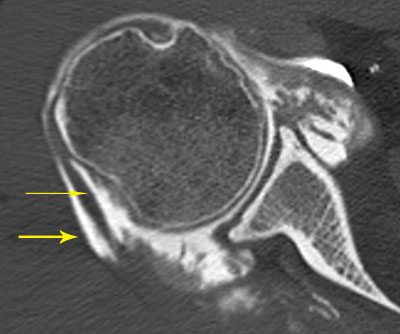

Arthroscanner correspondant (images 3 et 4)